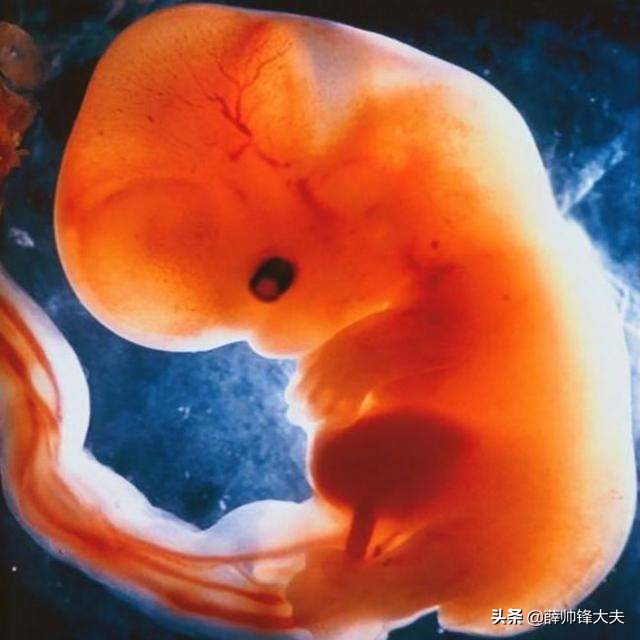

大约孕5周左右,正常的孕囊会有卵黄囊出现,孕早期的胚胎发育主要依靠卵黄囊,有了卵黄囊 1-2周内就会有胎芽、胎心,所以建议在8周左右检查通常都能看到胎心胎芽。

很多宝妈都经历过这种情况,有孕囊但是就是迟迟不出现心搏,这种情况叫做空卵,也就是种子有问题,是长不出胎心来的,所以在一定程度上讲胎心的出现才提示宝宝是存活了。

也有部分孕妈妈会有胎芽表现,而胎心一般在孕6–7周左右出现。 每个人情况不完全一样的,比如月经周期长短不一样,卵泡期不一样长,排卵的时间不一样,那么受精着床的时间也就不一样,还有孕囊发育成长的速度与孕妇本人未怀孕前的身体素质、卵泡质量以及怀孕之后的饮食、营养摄入等等都是有密切关系的。